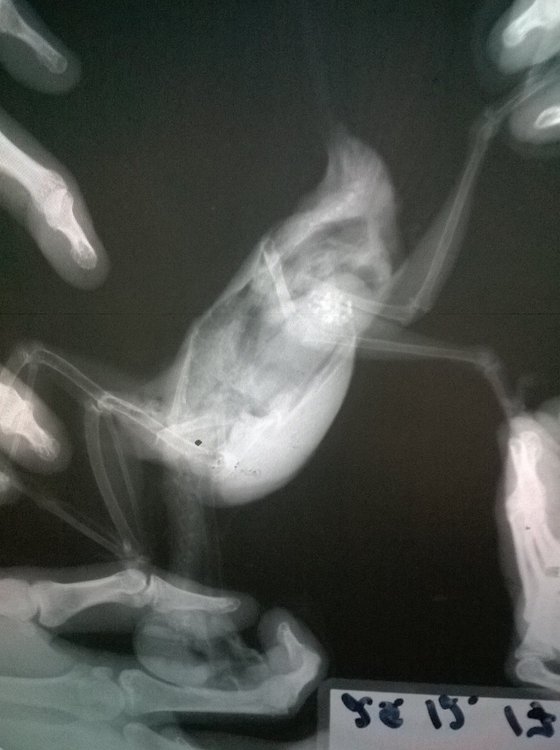

Неразлучник перестал летать, когда посмотрела, обнаружила на внутренней стороне крыла шишечку, сделали рентген, фото прикладываю. Не летает, крыло отпустилось и дрожит, продолжается больше месяца, обратиться больше не к кому, у нас нет специалистов в городе. Помет у попугая не менялся, активность хорошая, кушает тоже хорошо -